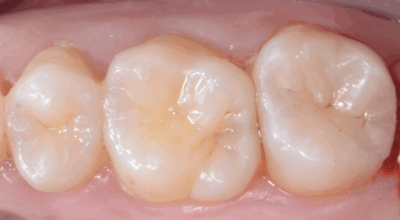

Clinical case

Partial pulpotomy: 88.2% success rate